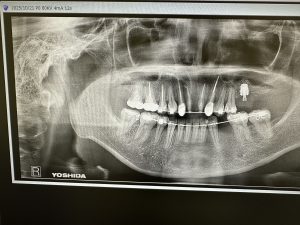

朝からインプラントオペ

左上7番、デンサーリフト、20分で終わり

手前6番は5年前のインプラント